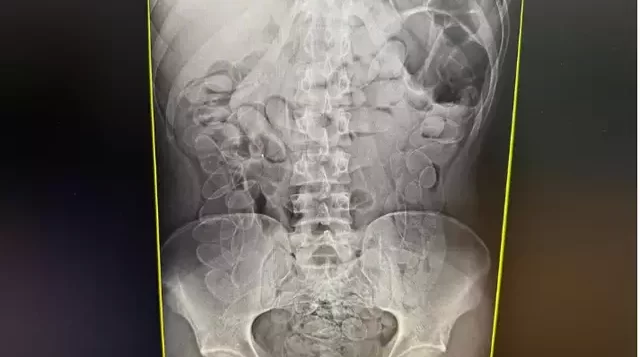

A Polícia Militar foi acionada por volta das 10h para comparecer ao pronto-socorro do município. Segundo a equipe médica, a própria paciente confessou ter ingerido os entorpecentes em território boliviano há cerca de uma semana, permanecendo com o material no organismo durante todo esse período. Um exame de raio-X confirmou a presença de múltiplos invólucros na região abdominal.